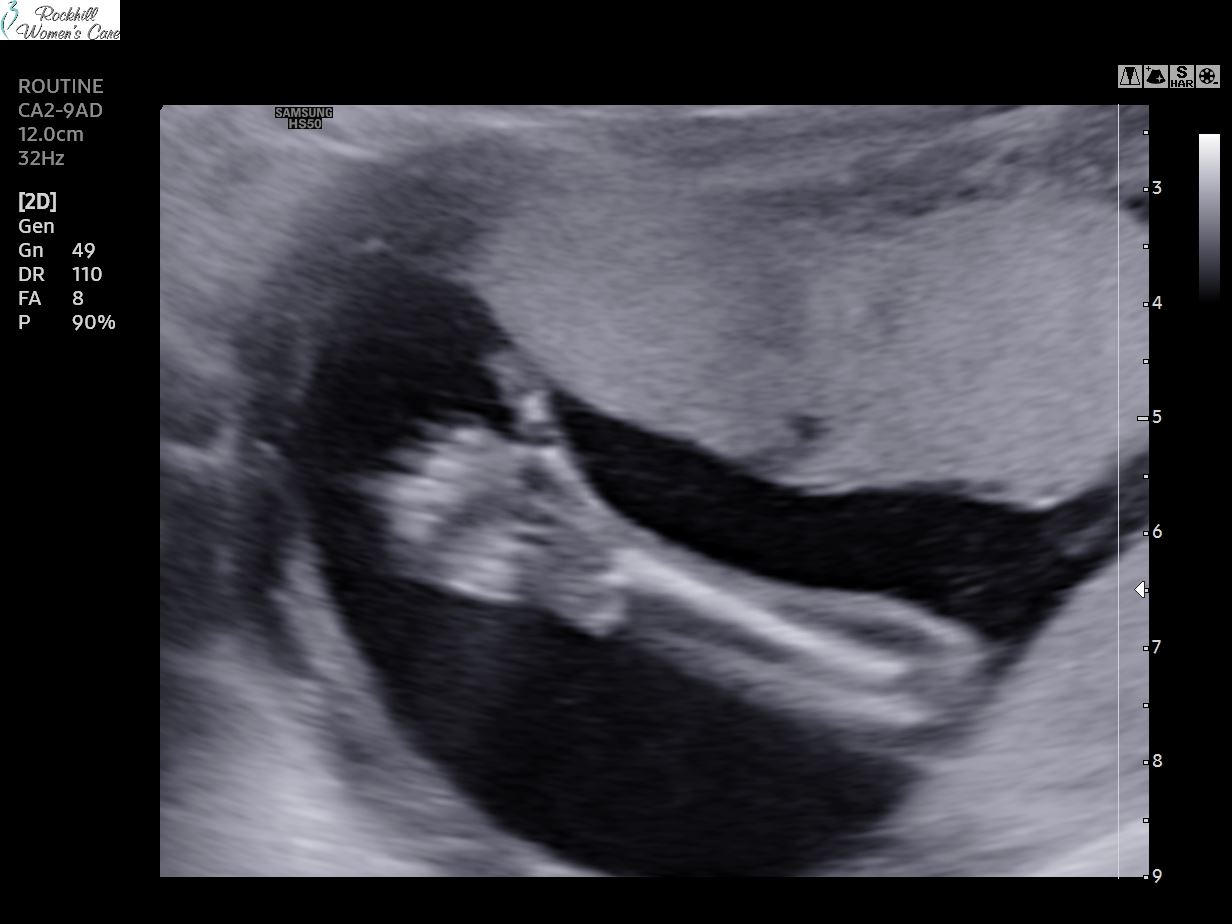

Little man wants cooperating so likely have to go back for spine pics